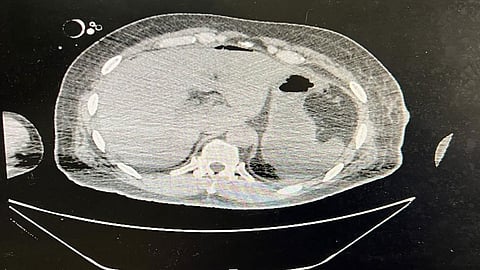

وأوضح استشاري الجراحة العامة الدكتور محمد مرزا أن المصاب حضر الى قسم الطوارئ والحوادث في حالة حرجة وهو يعاني من إصابة إثر تعرضه لطعنات بآلة حادة مع هبوط حاد في ضغط الدم، وعلى الفور تم نقله الى غرفة العمليات كحالة إنقاذ حياة وأجريت له عملية استكشافية للبطن بمشاركة قسم التخدير واتضح وجود قطع في عضلة الكتف ونزف داخلي ونزف شديد في الطحال والبنكرياس والاثنا عشر مع إصابة في القفص الصدري.

وأجري للمريض عملية استئصال للطحال وخياطة العضلات والجلد للكتف والسيطرة على النزف الدموي في التجويف البطني والصدر وإيقاف نزف البنكرياس والاثنا عشر.